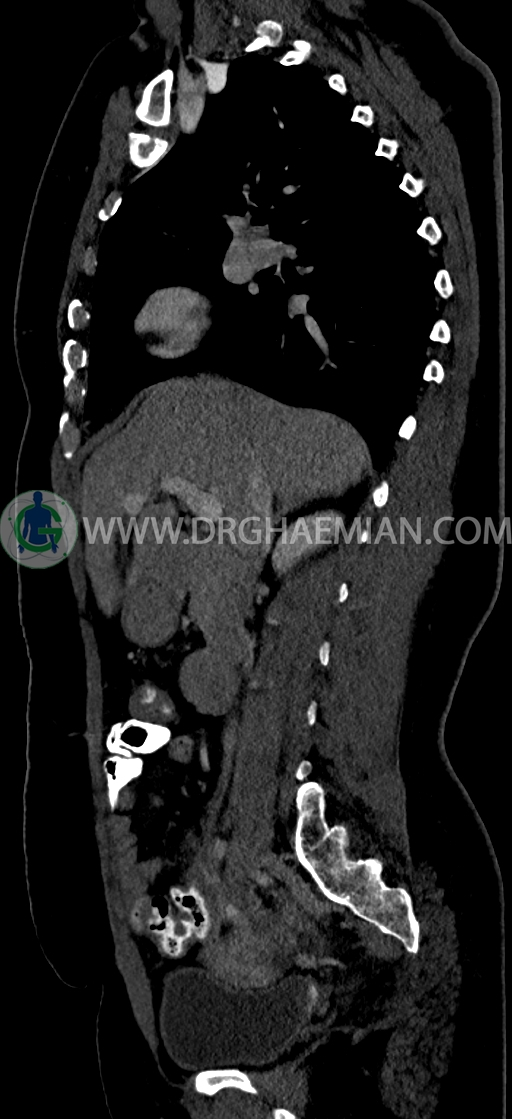

سی تی اسکن شکم و لگن یکی از روش های تصویربرداری با سی تی اسکن است. این روش با استفاده از اشعات ایکس تصاویر عرضی از ناحیه شکمی و لگنی ایجاد میکند. در این کیس سی تی اسکن هیپراستوز اسکلتی ایدیوپاتیک منتشر (DISH)، فیبروم اینترامورال، هرنی سوپرا امیلیکال دیده می شود.

در سي تي اسکن اسپيرال ريه و مدياستن-شکم و لگن با کنتراست خوراکی و وريدی (مولتي ديدکتور 16 با مقاطع ظريف و بازسازي هاي ساژيتال و کرونال) :

–Bridging osteophyte در مهره هاي توراسيک مطرح کننده DISH همراه با کيفوز مشهود است.

–lumbosacral transitional vertebrae

-هرني سوپرا امبليکال با ديفکت به سايز 10mm حاوي چربي و هرني امبليکال با ديفکت به سايز 7mm حاوي چربي مشهود است.